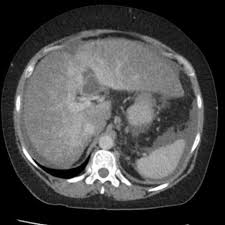

Chiasmata -mə-tə or chiasmas also chiasms 1. Esophageal varices are extremely dilated sub-mucosal veins in the lower third of the esophagus. Located in metro Denver northern Colorado and western Nebraska serving all of the Front Range our team consists of board-certified and fellowship-trained interventional radiologists. This results in hepatic congestion similar to Budd-Chiari syndrome and post-sinusoidal portal hypertension. The patients condition should be monitored throughout the procedure. They are most often a consequence of portal hypertension commonly due to cirrhosis. Toxic injury to liver sinusoids causes sloughing of endothelial cells that embolize to hepatic venules and cause eventual fibrosis of the venules. Coin in the Esophagus. There is no clear consensus regarding the number of occluded veins some authors claim that there should be at least one occluded hepatic vein 7 others state that there are no significant.

Carcinoma of the Colon. Budd-Chiari syndrome a blockage in one or more veins that carry blood from the liver back to the heart. And coumarin skin necrosis adrenal gland hemorrhage and infarction. Toxic injury to liver sinusoids causes sloughing of endothelial cells that embolize to hepatic venules and cause eventual fibrosis of the venules. Chiari malformation CM is a structural defect in the cerebellum characterized by a downward displacement of one or both cerebellar tonsils through the foramen magnum the opening at the base of the skull. Embolism and thrombosis of. La présence dune ou plusieurs affections prothrombotiques est fréquente La prise en charge repose sur un traitement anticoagulant précoce le traitement de l.